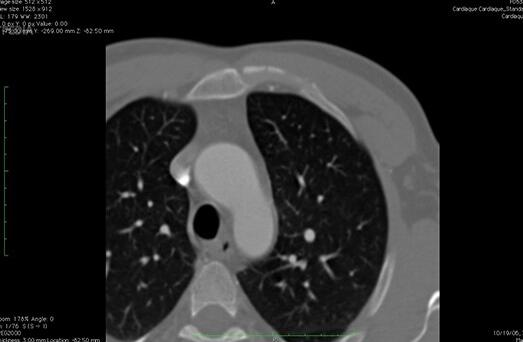

HorosMAC版是一款优质便利的开源医学图像查看软件。HorosMAC最新版帮助医学从业者,能够使您浏览可视化流行格式的医学图像库。HorosMAC版还能够指定的导出到文件夹之中,随时进行快速添加让您在医学的图像领域可以获得质的飞越,为用户提供优质服务。

想看个片子拍不清楚怎么办?如何提供最佳清晰的影响呢?Horos Mac版会提供开源医学图像查看器可以随时的进行导入以及导出来获得原始文件的链接.通过Horos Mac版还能够指定的导出到文件夹之中,随时进行快速添加让您在医学的图像领域可以获得质的飞越。帮助医护人员更好地学习医疗知识、诊断患者病情。

Horos Mac版是一个开源项目,支持大多数开源医学图像标准。是一个具有强大的导入和导出选项的医疗图像查看器。要开始使用Horos查看器,您必须首先通过复制或链接原始文件导入映像数据库。Horos还可以处理原始数据,并允许您使用在线资源。